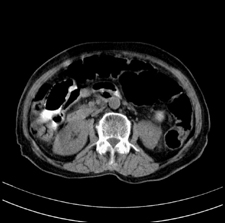

患者,女,75岁。腹痛,体黄5日,膝胸位时腹痛缓解。肝功能明日出来。彩超提示胆总管占位,未见血流信号。心电图提示s-t段改变。患者体质较弱,未能增强。

胆总管多发结石伴肝内外胆管轻度扩张。

胆总管上段,腔内有软组织密度影 ,ct值36-44hu。大家看有没有胆管癌的可能。

肝囊右.肾上腺囊肿

胆总管多发结石伴肝内外胆管扩张。

胆管结石并发胆管炎。

支持 胆总管结石,左侧胸膜增厚,心包膜增厚。